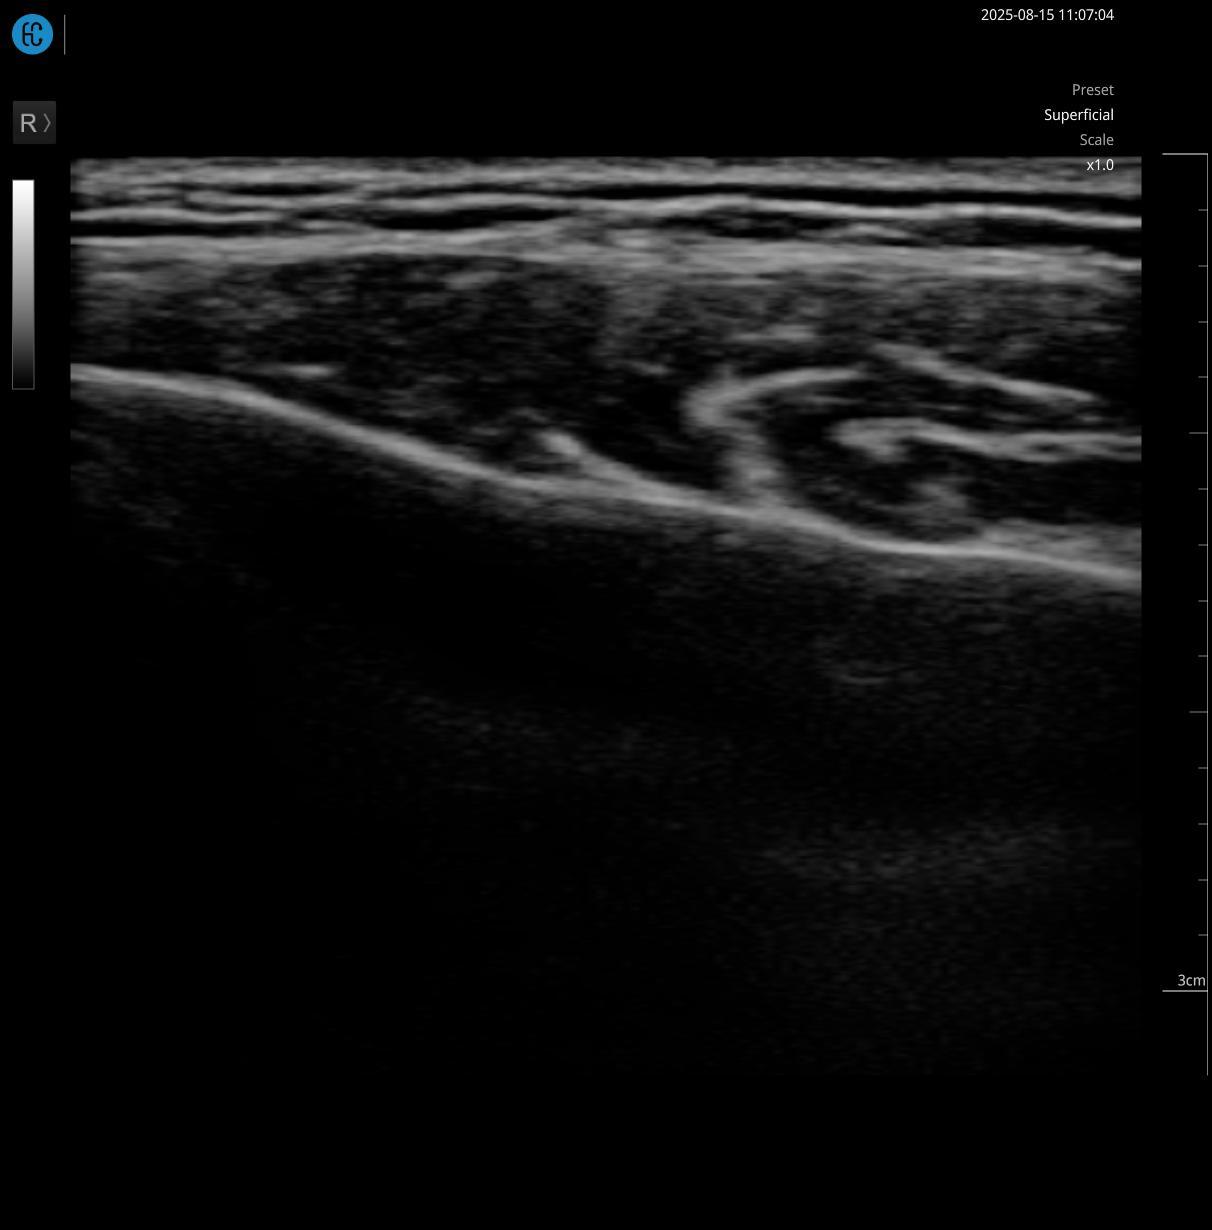

USG Skin adalah teknologi diagnostik yang digunakan untuk melihat struktur kulit wajah secara mendalam, bukan hanya di permukaan. USG Skin bukan sekadar teknologi tambahan, tetapi standar keamanan dan presisi dalam dunia aesthetic medicine modern. Di Amala Clinic, USG Skin ini tersedia dengan nama DEEP SON DIAGNOSE dan dilakukan sebagai langkah awal sebelum pasien melakukan treatment injeksi.

Treatment injeksi seperti botulinum toxin, filler, maupun skin booster bekerja di lapisan dan struktur tertentu. Tanpa pemahaman anatomi individual pasien secara mendalam, risiko hasil yang kurang optimal hingga komplikasi bisa meningkat.Tujuannya sederhana, memahami kondisi kulit lebih akurat sebelum menentukan tindakan, karena tidak ada dua wajah yang memiliki struktur anatomi yang benar-benar sama.

USG Skin membantu dokter melihat secara real-time:

- Ketebalan dan kedalaman kulit (dermis)

- Struktur jaringan di bawah kulit

- Posisi pembuluh darah

- Menentukan titik injeksi yang paling aman

Setiap wajah memiliki struktur yang berbeda, dan USG Skin membantu membaca perbedaan tersebut, untuk memberikan treatment yang aman, terukur, dan sesuai dengan kebutuhan unik setiap pasien.